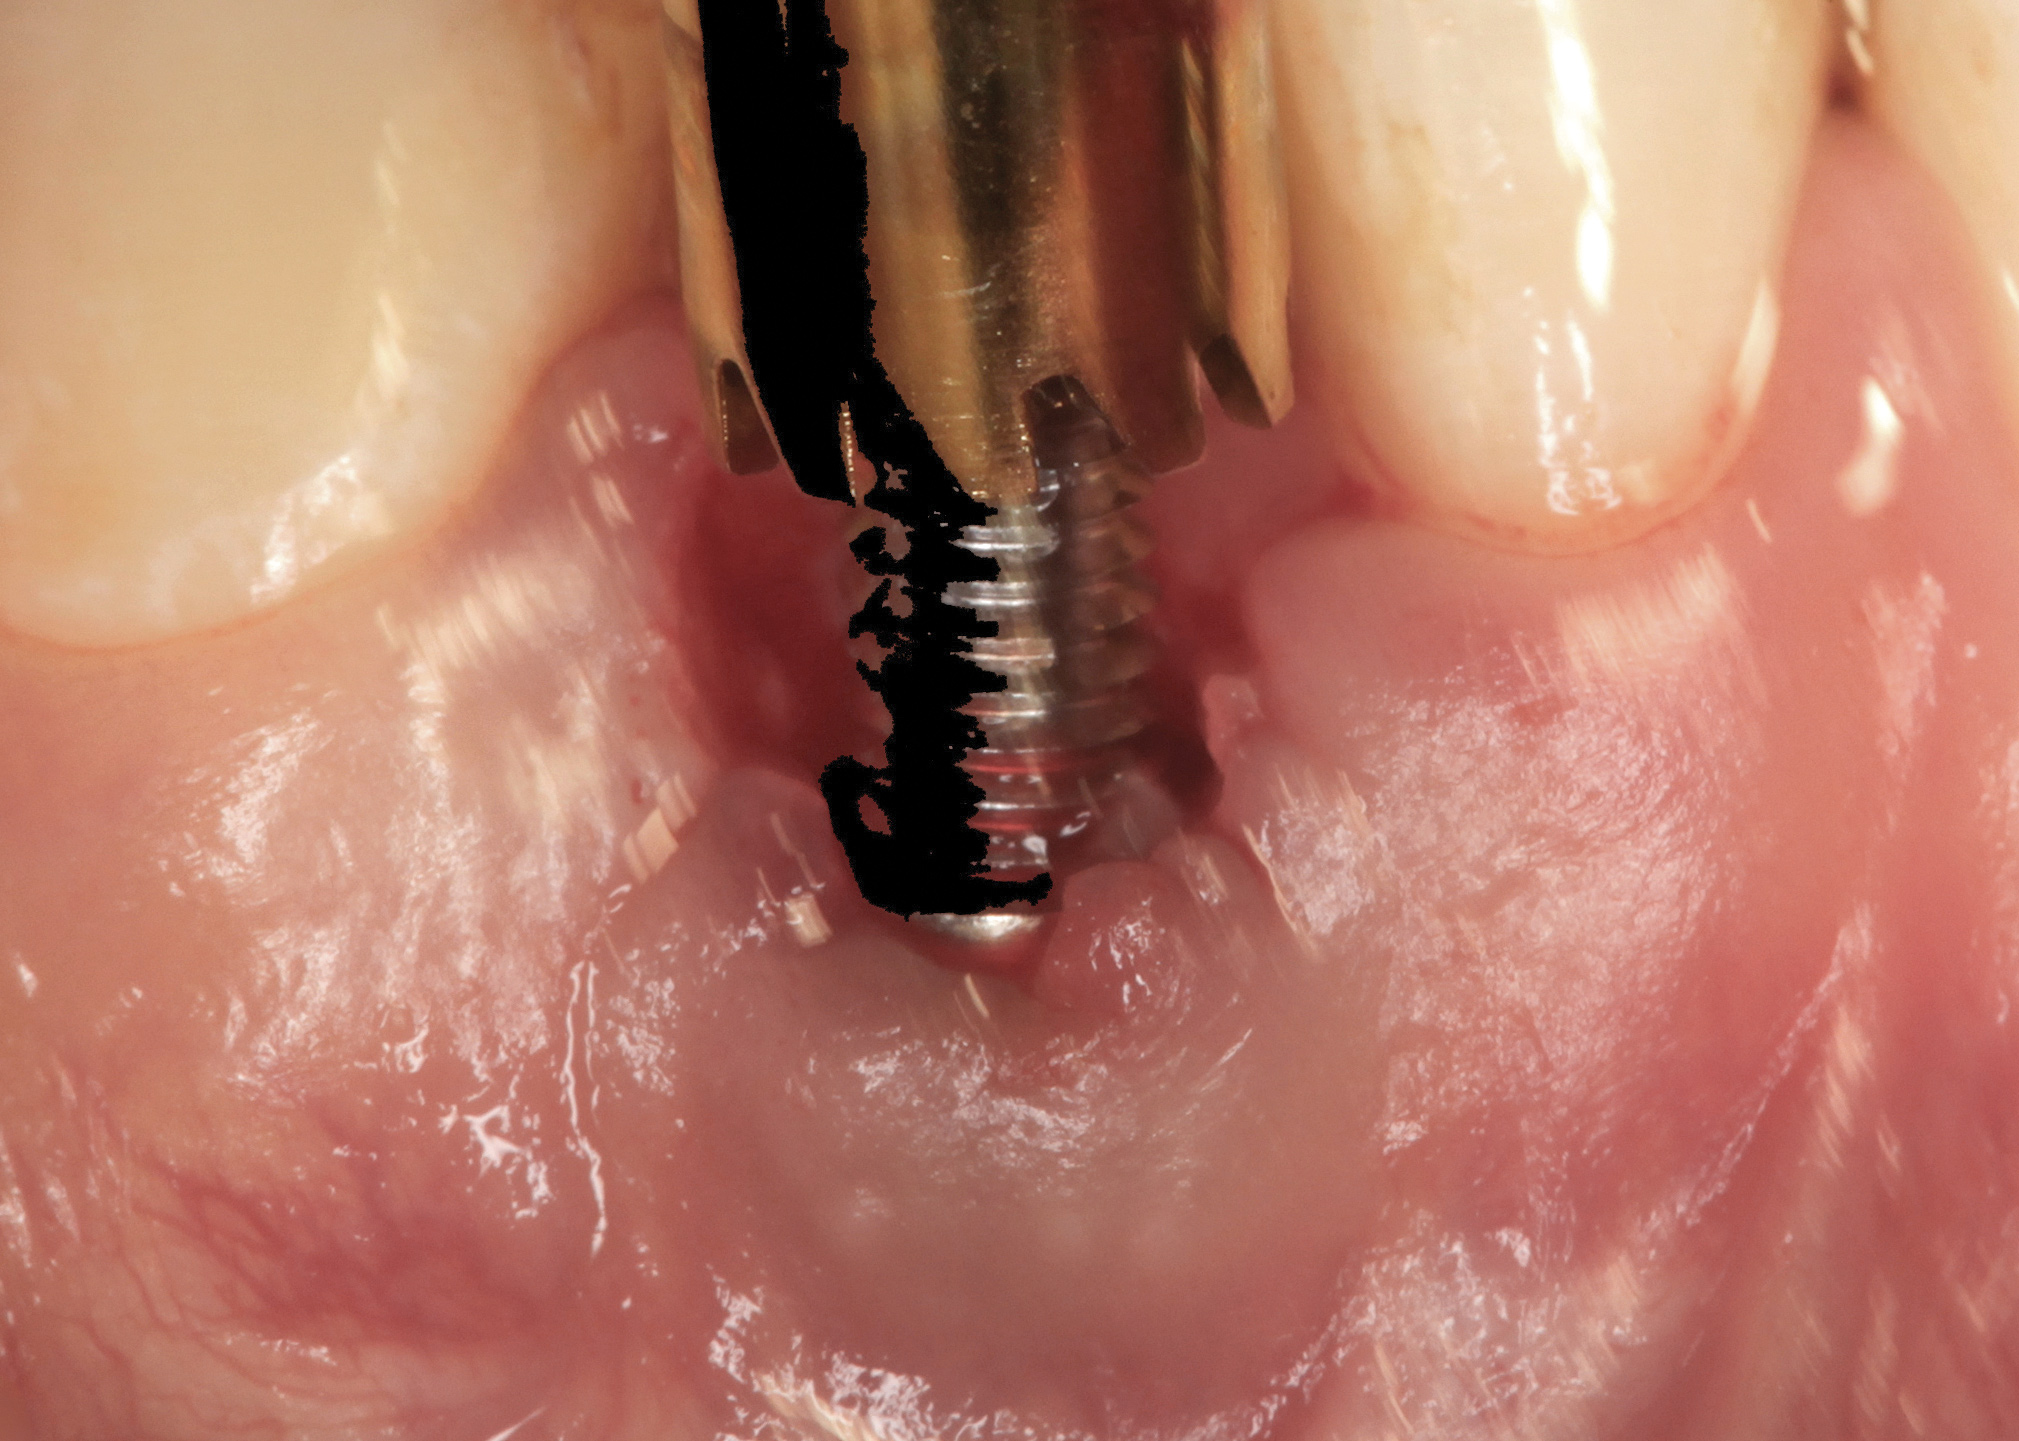

Fig 38. A reverse-torque screw was placed into the implant.

Figure 38

Fig 39. A counter-torque device was placed over the reverse-torque screw.

Figure 39

Fig 40. The implant was easily unscrewed within minutes in a minimally invasive manner with less trauma to the surgical site.

Figure 40

The crown and screw-retained custom abutment were removed, and a surgical cover screw was placed into the implant, thereby allowing spontaneous gingival augmentation in situ (Figure 33 and Figure 34). Note that the lingual aspect of the implant site was significantly more coronal than the labial aspect, which was positive because the defect would be limited to a facial–lingual defect. A fixed RBR bridge was cemented on the adjacent teeth and used as a tooth-supported transitional provisional restoration (Figure 35). A few weeks were allotted to let the soft tissue heal and migrate around the cover screw (Figure 36) to see if there would be complete coverage, thereby allowing a soft-tissue augmentation procedure to be performed with primary flap closure as in clinical scenario No. 2. The major obstacle in achieving a positive tissue response was that the implant depth was also deficient because the implant–abutment connection was at the level of the free gingival margin. It was decided that the best treatment option would be to remove the implant. A high-powered reverse-torque device (Fixture Remover Kit, NeoBiotech, www.neobiotechus.com) was used to remove the implant atraumatically (Figure 38 through Figure 41). The implant socket was allowed to heal for several months not unlike an extracted tooth (Figure 42). A new implant was placed in a better position from both a restorative and esthetic perspective (Figure 43), and after a few months of healing, a new crown was made (Figure 44). A satisfactory functional and esthetic result was achieved (Figure 45 and Figure 46) without employing pink porcelain.